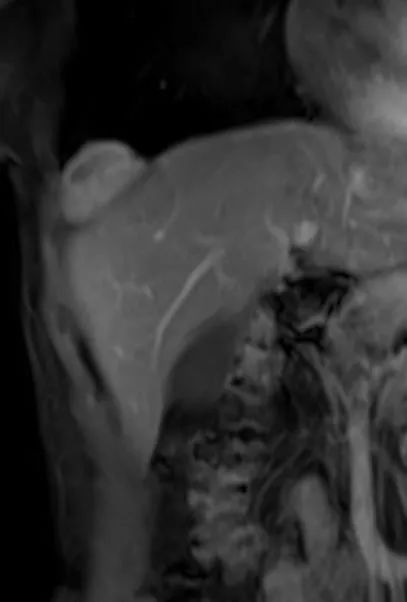

MR 检查更能反应肿瘤特性及与胸膜关系

T1WI 多呈等低或等信号,T2WI 信号变化多样,可同时有高低信号区

T2WI 高信号反映肿瘤黏液样变区,略高信号反映肿瘤细胞密集区,低信号区反映致密胶原纤维

增强不均匀强化